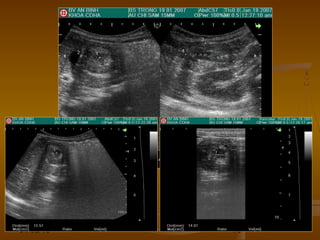

Abscess ruột thừaAbscess gan